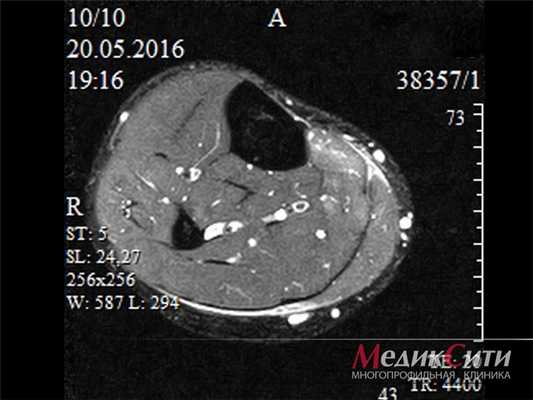

Дисфункция сухожилия задней большеберцовой мышцы

Этот синдром является причиной патологии медиальной части заднего отдела стопы, часто просмотренной и неправильно диагностированной, особенно на ранних стадиях. Это является прямым результатом потери функции сухожилия задней большеберцовой мышцы.

Хроническое воспаление ведет к дегенерации и растяжению сухожилия с формированием интерстициального отека, истончением и хроническим повреждением сухожилия. При отсутствии лечения все это ведет к нарушению выравнивания заднего и среднего отделов стопы с пронацией пятки, плантафлексии тарана, подвывиху в таранно-ладьевидном суставе и как результат формирование односторонней плоской стопы.

Задняя большеберцовая мышца активна в течение фазы опоры, включается сразу после контакта пятки с опорой и быстро прекращает сокращаться после поднятия пятки. Ее брюшко начинается глубоко внутри задней части нижней конечности, сухожилие следует вниз до задней части медиальной лодыжки, где находится кпереди от сухожилия длинного сгибателя пальцев, заднего большеберцового нейрососудистого пучка (задняя б/б артерия, вена и нерв) и сухожилия сгибателя большого пальца. Все эти структуры ограничиваются удерживателем сгибателей возле медиальной лодыжки. Сухожилие задней б/б мышцы проходит в борозде позади и ниже медиальной лодыжки, разделяясь на 3 части у медиальной стороны тарана. Передняя часть прикрепляется к бугристости ладьевидной кости, средняя часть продолжается в плантарную тарзальную область и прикрепляется к плантарной части клиновидных костей, кубовидной и в основании 2, 3 и 4 метатарзальных костей. Задняя часть внедряется как пучок в переднюю часть нижней пяточно-ладьевидной связки. Медиальная лодыжка работает как многороликовый блок, позволяя сухожилию задней б/б мышцы изменять направление тяги, и эти точки прикрепления обеспечивают супинацию заднего и среднего отделов стопы во время переноса веса, в то время как происходит стабилизация арочной конструкции среднего отдела.

МРТ наиболее полезный метод исследования сухожилий вокруг голеностопного сустава и выявления повреждений. Другие диагностические тесты включают сканирование костей и введение радиоконтрастного вещества в сухожильное влагалище.